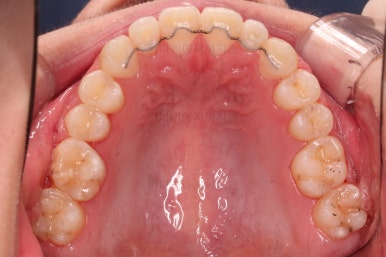

마찬가지로 초진 시 입안의 모습인데요.

위아래 앞니가 삐뚤고, 송곳니는 덧니처럼 불룩 튀어나가 있네요.

위아래 앞니는 안으로 굽어 들어와 있는 옥니(뻐드렁니 반대) 양상이었고요.

그리고 마무리 때 디테일에 문제가 생길 수 있는 부분인데, 윗니 대문니(가장 중간 치아)와 송곳니 사이의 치아를 작은 앞니라고 하는데요.

이 작은 앞니가 가져야 될 크기보다 더 작은 양상이었습니다.

이런 치아를 왜소치라교 표현합니다.

유지장치를 잘 부착하고요.

왜소치가 있어서 중앙선과 교합을 맞추는데 약간의 애로사항이 있었지만 최대한 잘 마무리를 하였습니다.

앞니 각도, 가지런한 느낌, 덧니 등 모든 점이 다 개선되었네요.